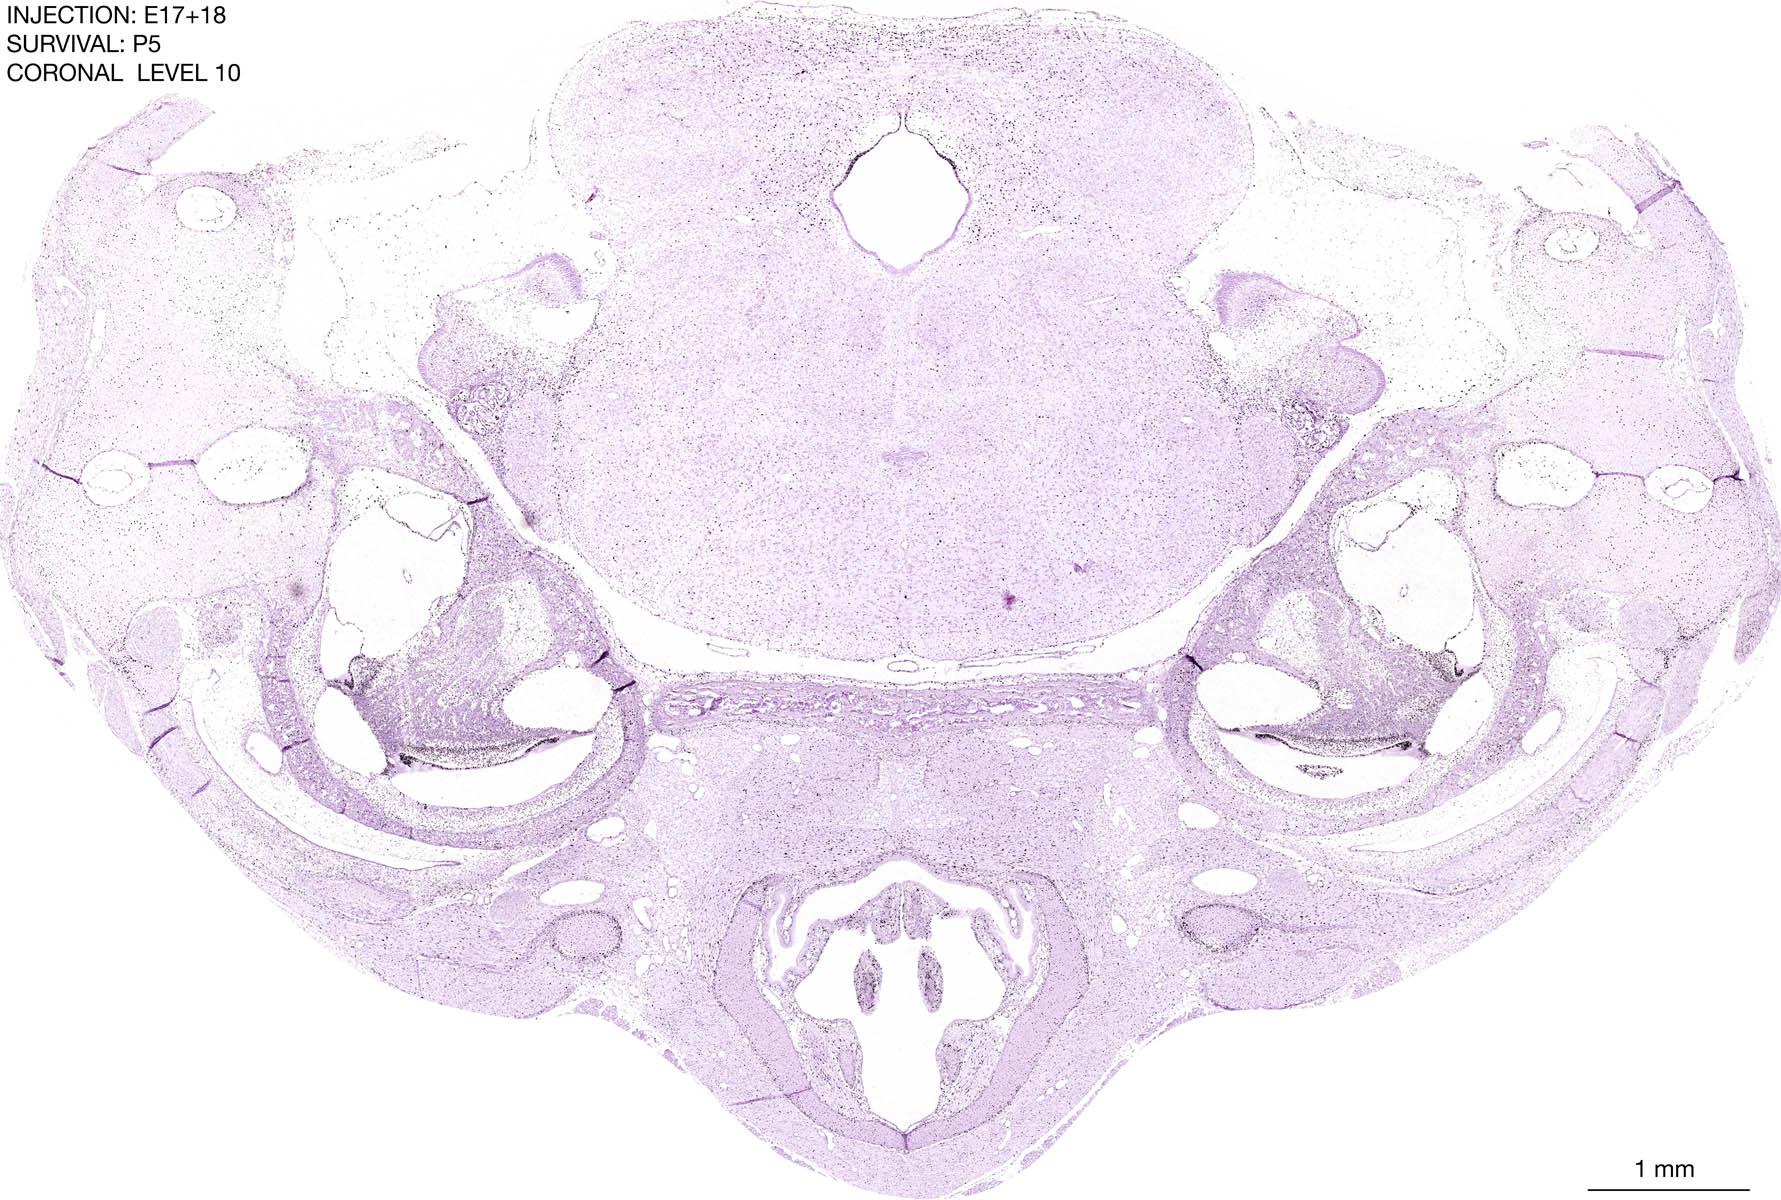

E17+18 P5 Survival The images below are from the brain of a rat that was exposed to tritiated thymidine on E17+18 and survived to P5. Download: Large | High Res Download: Large | High Res Download: Large | High Res Download: Large | High Res Download: Large | High Res Download: Large | High Res Download: Large | High Res Download: Large | High Res Download: Large | High Res Download: Large | High Res Download: Large | High Res Download: Large | High Res Download: Large | High Res Download: Large | High Res Download: Large | High Res Download: Large | High Res Download: Large | High Res Download: Large | High Res Download: Large | High Res Download: Large | High Res Download: Large | High Res Download: Large | High Res Download: Large | High Res Download: Large | High Res Download: Large | High Res Download: Large | High Res